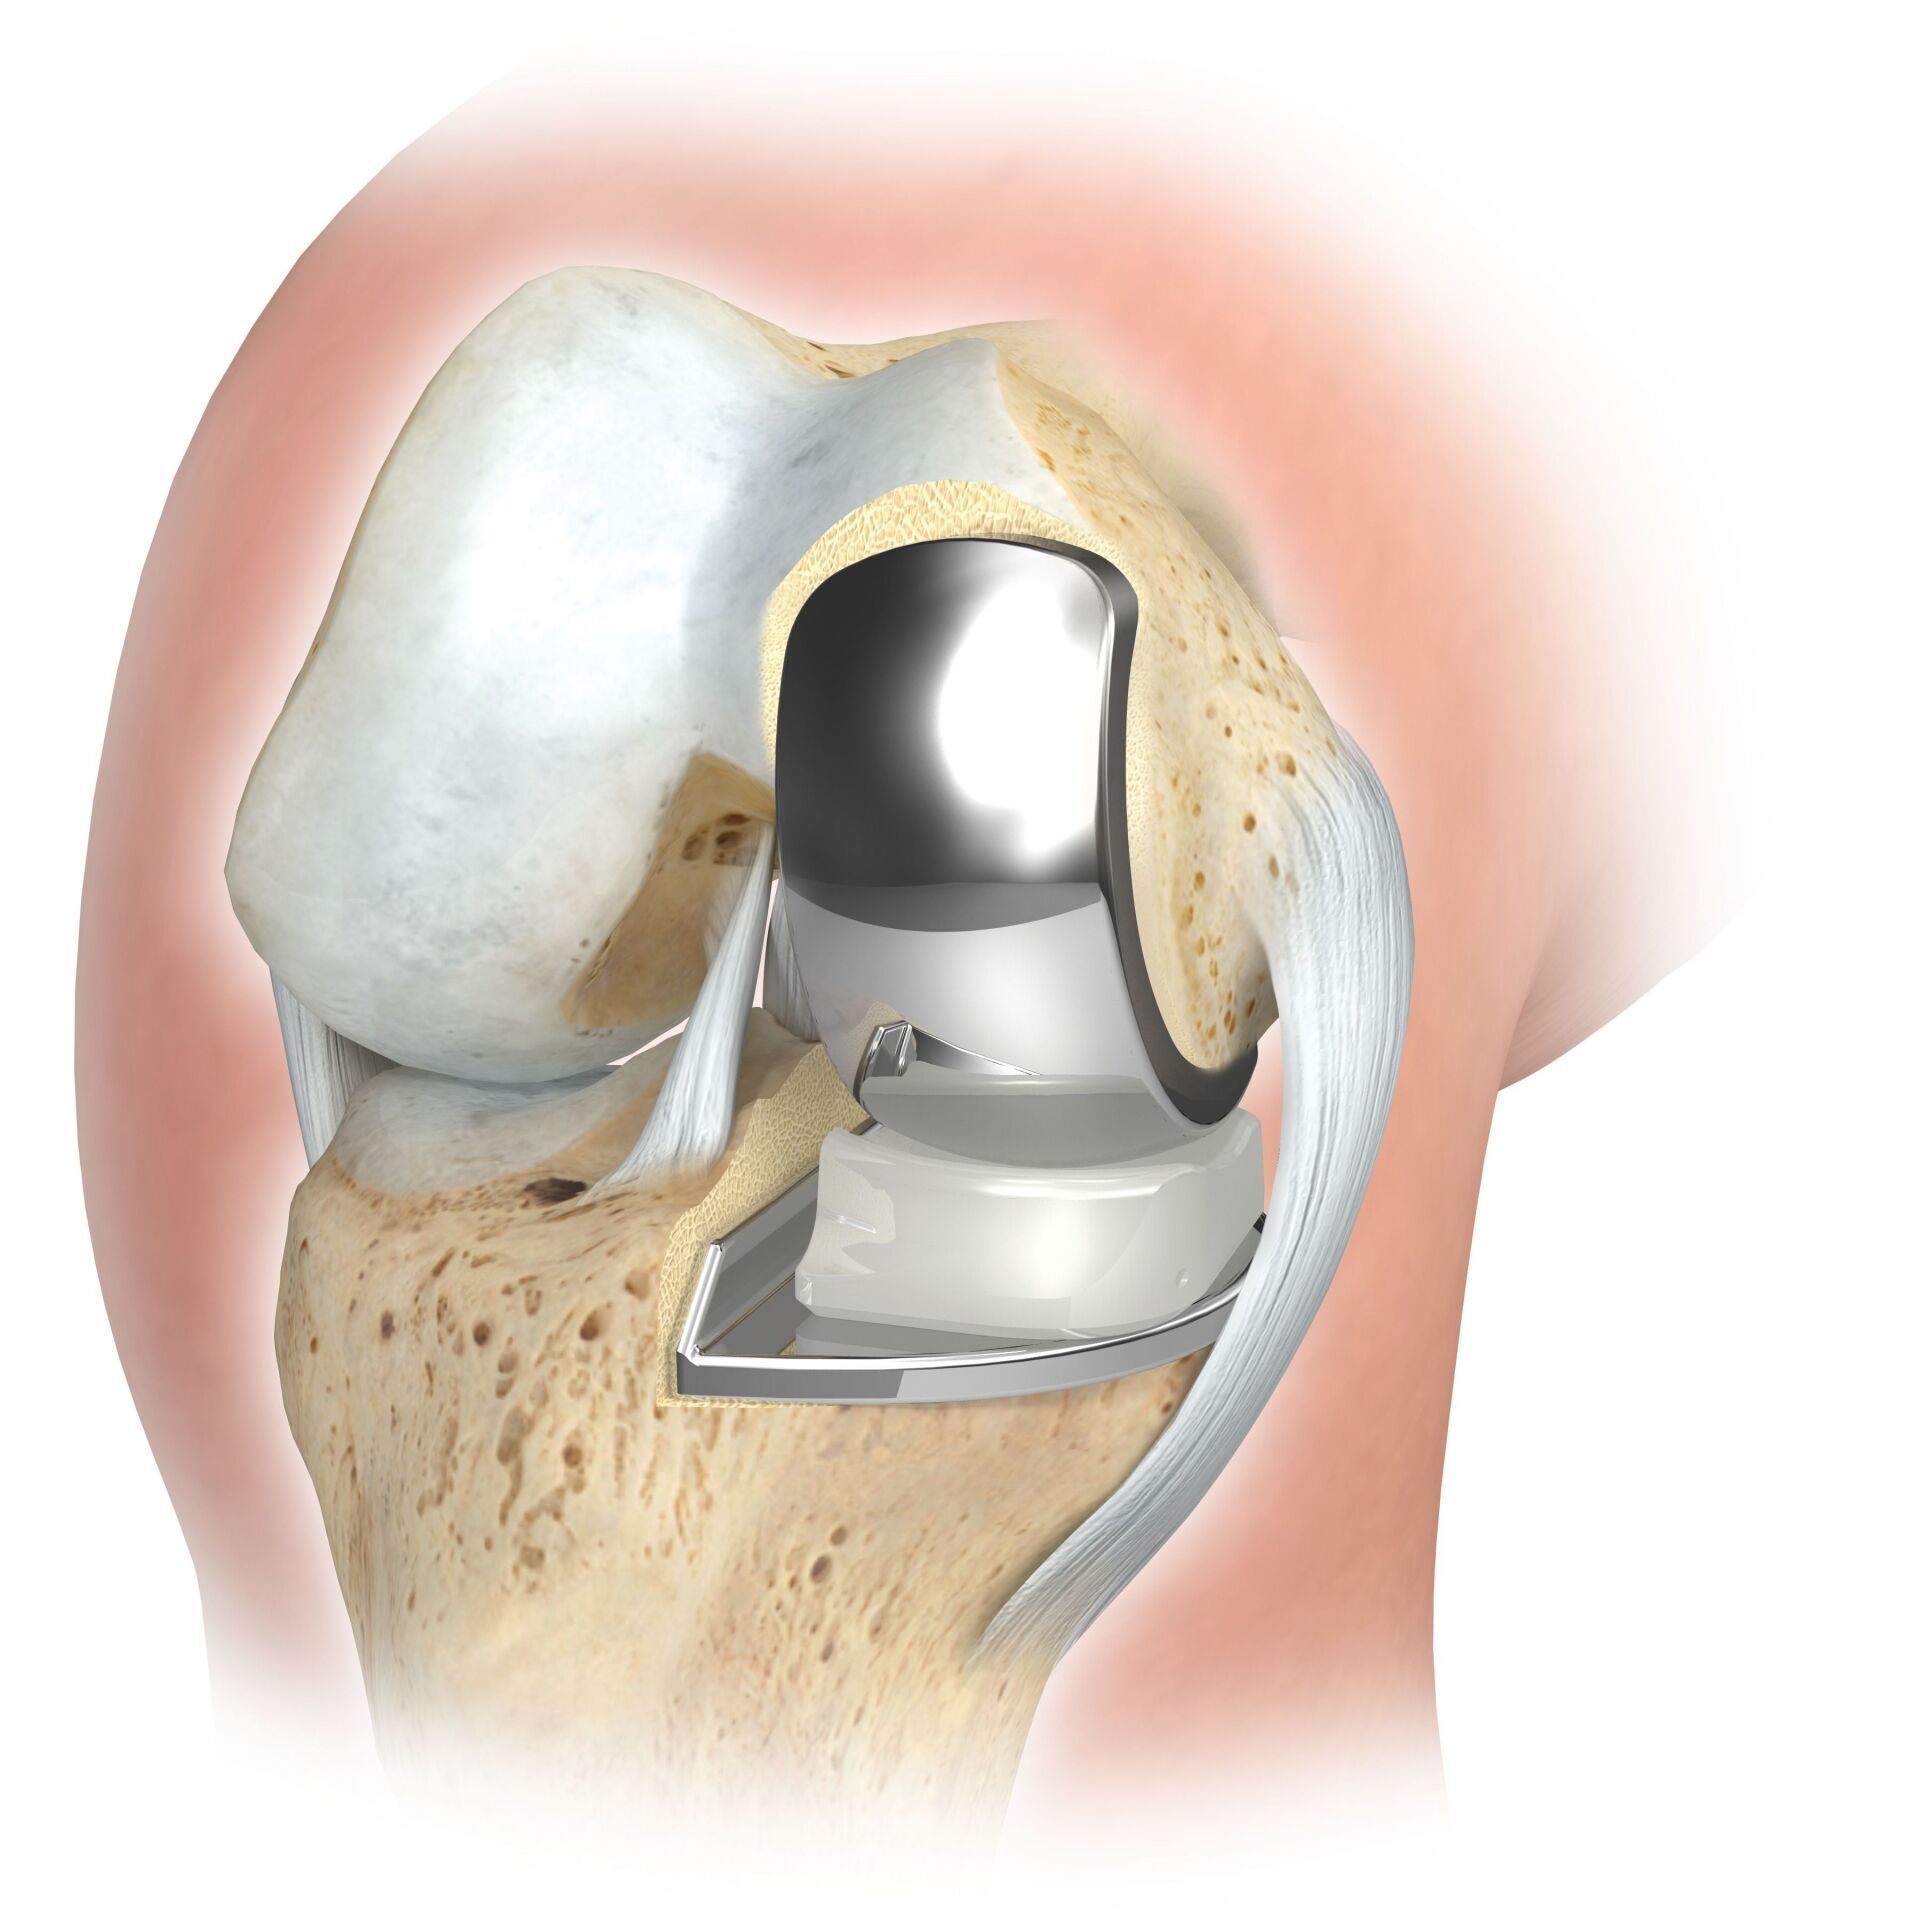

Das künstliche Kniegelenk ersetzt die durch die Arthrose zerstörte Knorpeloberfläche. Der darunterliegende Knochen am Oberschenkel und Schienbeinkopf bleibt erhalten. Manche vergleichen ein modernes künstliches Kniegelenk mit einer

Überkronung bei einem Zahn, der genaue Begriff ist der sogenannte

bikondyläre Oberflächenersatz. Zwischen den neuen Oberflächen am Ober- und Unterschenkel befindet sich das sogenannte Inlay aus einem speziell verhärteten weißen Kunststoff, das im Röntgenbild als Abstand zwischen den Metallteilen zu erkennen ist.

Bei der Operation erfolgt der Zugang zum Kniegelenk von der Vorderseite und das Knie wird während der OP mehrfach gebeugt und gestreckt. Die Außen- und Innenbänder und teilweise auch die Kreuzbänder werden während der Operation sorgfältig geschützt.